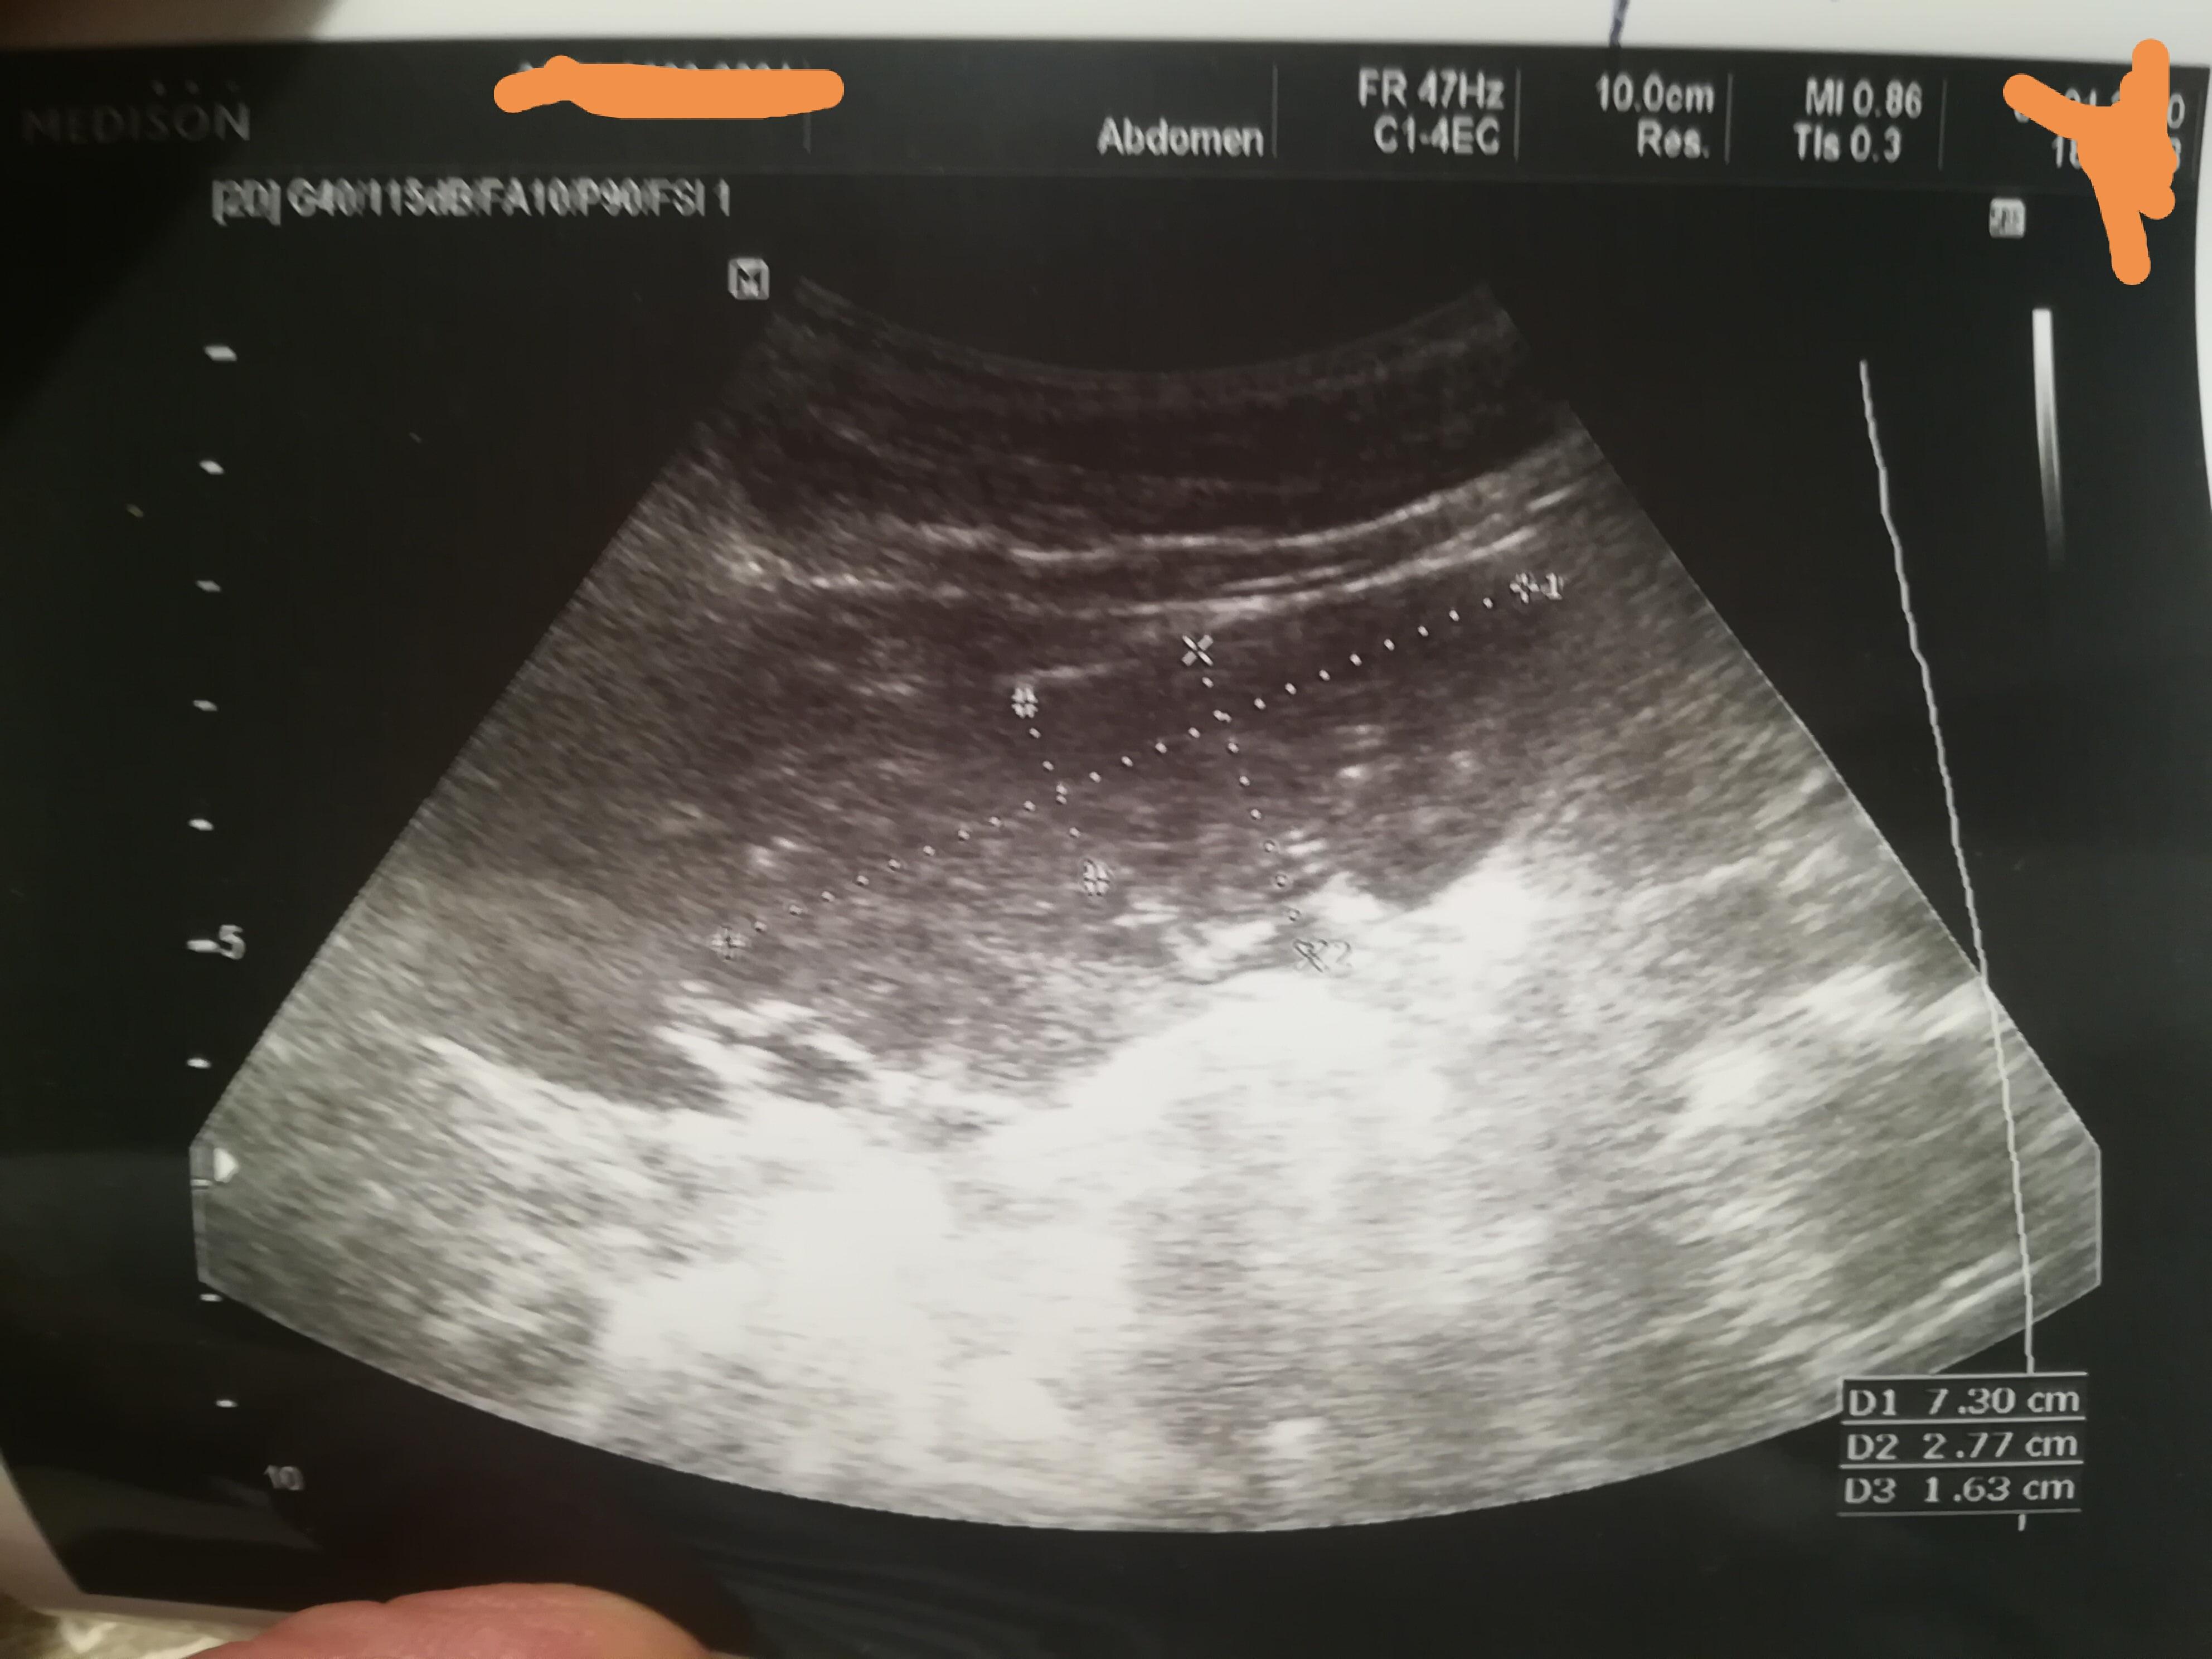

L-образная почка

Добрый день! Дочери 5 лет случайно обнаружили L образную почку. Жалоб никаких нет. Размеры в норме. Анализ крови и мочи в норме. Стоит ли проходить дополнительные обследования. Какой обычно прогноз при данной аномалии? Можно ли заниматься физкультурой, танцами и т.д.? Возможно ли иметь детей в будущем с такой проблемой? Спасибо!

Здравствуйте! Сейчас ничего больше предпринимать не надо. Раз в год делать УЗИ почек, анализ мочи - согласно плановым обследованиям.